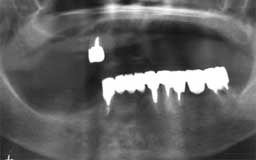

Eさん 初診時 53歳 女性

残存歯数26本とはいえ、10代のころみたいな万全な状態の歯は1本もなく、クラウンの中は 虫歯、歯周疾患も末期の状態です。徹底的な治療とメインテナンスが必要と思われます

Eさん 12年後 65歳

治療やメインテナンスに対する理解が得られず、主訴のみの治療で来院が途絶えてしまいまし た。その後他院を転々と受診したそうですが、約10年間に予想通り大半の歯を喪失

Eさん 17年後 70歳

再来院後は毎月のメインテナンスを継続され、今のところ何とか残存歯がそのまま機能してい ます